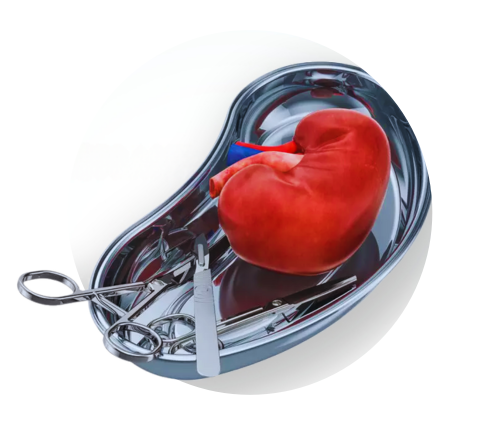

Interventional Nephrology

Advanced Procedures for Urgent Kidney Care

Interventional Nephrology focuses on performing minimally invasive, life-saving kidney-related procedures in emergency and critical care settings. These interventions help stabilize patients with severe kidney dysfunction, manage complications, and enable safe dialysis access when urgently required.